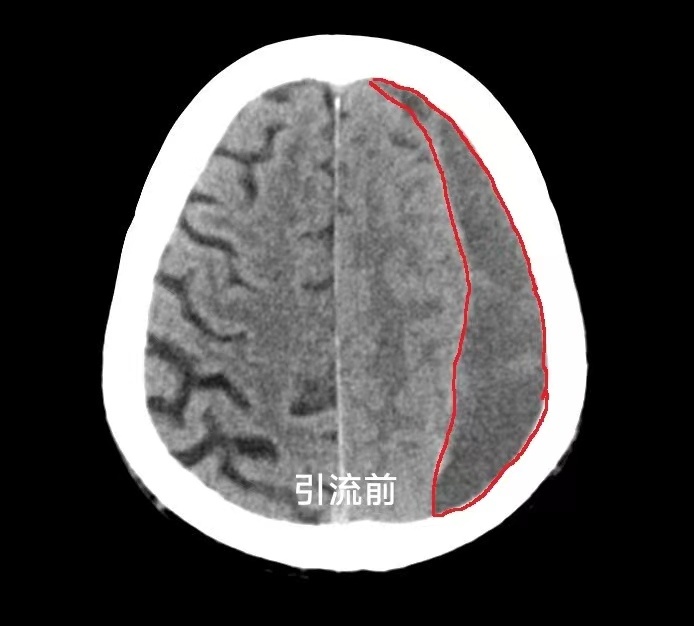

经神经外科会诊后复查头部CT,发现颅内积血比之前更多了,脑组织受压非常严重,神经外科杜秀玉主任团队和家属沟通后决定用快速“微创引流技术”将颅内血肿排出来,不需要全麻,也不需要开刀。

整个手术过程在局部麻醉下进行,仅在头皮注射一针麻药,将引流穿刺针经头皮颅骨穿刺进入血肿部位通过引流管将出血排出体外。手术操作过程约 10 分钟,术后患者头昏肢体无力症状明显改善,术后一天,神志也清楚了,可以正常交流,不能动弹的肢体活动自如,复查头颅 CT 可见颅内积血已基本完全引流出来。